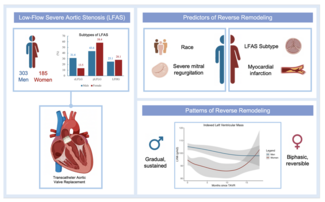

Abstract: A 59-year-old male underwent coronary artery bypass grafting and mitral ring annuloplasty 4 years ago. The procedure was complicated by sternal wound infection. Recently, he presented with multiple admissions for decompensated heart failure with volume overload and pulmonary edema. He was found to have severe mitral regurgitation (MR) and transesophageal echocardiography (TEE) demonstrated severe MR through an anterior mitral leaflet perforation. Due to high surgical risk, he was referred for transcatheter repair of his mitral valve. This case illustrates the first reported use of an Amplatzer atrial septal occluder device for percutaneous mitral leaflet repair using three-dimensional TEE guidance after prior surgical mitral ring annuloplasty repair.

Mitral leaflet perforation and mitral ring annuloplasty dehiscence occur rarely after surgical mitral valve repair, and are related to technical factors, suture failure, tissue quality, and endocarditis.1-3 For patients with clinical symptoms, surgical reintervention is generally warranted. However, reoperation after mitral valve repair or replacement is associated with a mortality rate that approaches 12%.2,4 Numerous case series and reports have described percutaneous approaches to the management of mechanical or bioprosthetic mitral paravalvular leaks.5,6 Although there has been one reported case of an anterior leaflet perforation treated with an Amplatzer septal occluder after aortic valve replacement, there have been no prior reports describing percutaneous repair of mitral leaflet perforation after surgical mitral valve annuloplasty repair.7 We describe a case of successful percutaneous repair of an anterior mitral leaflet perforation in a high-risk patient who had previously undergone mitral ring annuloplasty.

A 59-year-old man was referred to our institution for potential MitraClip (Abbott Vascular) therapy after he was found to have severe mitral regurgitation (MR) seen on transthoracic echocardiography. He had a history of coronary artery disease and functional MR, and underwent coronary artery bypass grafting and mitral annuloplasty (28 mm CG Future; Medtronic Inc.) 4 years prior at an outside institution. A permanent pacemaker was also implanted for advanced atrioventricular block. The procedure was complicated by a methicillin-resistant  staph aureus sternal wound infection requiring multiple debridements and wound vacuum drainage for 1 year. There was no documented bacteremia at that time. Three years later, he had several admissions for decompensated heart failure, volume overload, and pulmonary edema without angina pectoris. Transthoracic echocardiogram revealed left ventricular (LV) ejection fraction of 55%, severe MR with 2 distinct regurgitant jets, and an estimated right ventricular pulmonary systolic pressure of 60 mm Hg. Subsequent transesophageal echocardiography (TEE) demonstrated a dilated mitral annulus with the septal-lateral dimension measuring 36 mm. There was significant dehiscence of the annuloplasty ring from the posterior annulus and focal dehiscence at the right fibrous trigone, with a resultant 6 x 8 mm perforation at the base of the anterior mitral leaflet (Figure 1). There was 4+ MR through the mitral leaflet perforation and 1+ central MR. There was trivial regurgitation through the posterior dehiscence (Figure 2). After referral to our center, 3.5 years after the original operation, several blood cultures drawn on different days were negative and an erythrocyte sedimentation rate was normal. Angiography demonstrated occluded vein grafts to the left circumflex and right coronary arteries with severe native diffuse disease not amenable to percutaneous or surgical revascularization. The left internal mammary artery graft to left anterior descending artery was patent. In view of his related comorbidities and prior sternal wound infection, percutaneous repair of the anterior mitral leaflet perforation was performed.

staph aureus sternal wound infection requiring multiple debridements and wound vacuum drainage for 1 year. There was no documented bacteremia at that time. Three years later, he had several admissions for decompensated heart failure, volume overload, and pulmonary edema without angina pectoris. Transthoracic echocardiogram revealed left ventricular (LV) ejection fraction of 55%, severe MR with 2 distinct regurgitant jets, and an estimated right ventricular pulmonary systolic pressure of 60 mm Hg. Subsequent transesophageal echocardiography (TEE) demonstrated a dilated mitral annulus with the septal-lateral dimension measuring 36 mm. There was significant dehiscence of the annuloplasty ring from the posterior annulus and focal dehiscence at the right fibrous trigone, with a resultant 6 x 8 mm perforation at the base of the anterior mitral leaflet (Figure 1). There was 4+ MR through the mitral leaflet perforation and 1+ central MR. There was trivial regurgitation through the posterior dehiscence (Figure 2). After referral to our center, 3.5 years after the original operation, several blood cultures drawn on different days were negative and an erythrocyte sedimentation rate was normal. Angiography demonstrated occluded vein grafts to the left circumflex and right coronary arteries with severe native diffuse disease not amenable to percutaneous or surgical revascularization. The left internal mammary artery graft to left anterior descending artery was patent. In view of his related comorbidities and prior sternal wound infection, percutaneous repair of the anterior mitral leaflet perforation was performed.

MR is one of the most commonly encountered valvular lesions in clinical practice, with 6.4% of the general population ≥65 years having at least moderate MR.8 Moderate-severe MR is present in 15-30% of patients with congestive heart failure and up to 12% of patients within 1 month after myocardial infarction. Since MR severity has been positively correlated with the subsequent development of heart failure and death, patients are often referred for surgical or percutaneous repair.9-12 The patient we have presented had functional MR (FMR), which is a consequence of underlying LV dysfunction or annular dilation. These derangements in the mitral apparatus impair the coaptation of leaflets which are otherwise structurally normal. Surgical correction of FMR with mitral annuloplasty rings has been shown to improve functional class and LV remodeling, but a survival benefit has yet to be proven.13,14 Additionally, even with current surgical annuloplasty techniques, up to 35% of treated patients have moderate or greater MR recur within 1 year of surgery.15-17

Because of the technical complexity of mitral valve repair, these remain challenging procedures for the cardiovascular surgeon. Mechanisms of late mitral repair failure include progression of degenerative changes of the leaflets and chordae tendineae, suture dehiscence, and endocarditis.1,18 As endocarditis is often associated with cardiac valve leaflet perforation and erosion, infection must be excluded in all patients with leaflet perforation, suture dehiscence, or paravalvular leak. In the reported case, multiple blood cultures drawn over several weeks after referral to our center were negative, and no vegetations were seen on TEE. The perforation in this case could have been the result of excessive suture tension, or from prior endocarditis following the original surgery complicated by severe sternal infection. Surgical intervention for leaflet perforation remains the treatment of choice in most patients. Sareyyupoglu and colleagues reported a series of 26 subjects with anterior mitral leaflet perforation who underwent surgical repair.19 Ninety-two percent of these patients had a history of endocarditis. Surgical repair with primary suture closure (n = 15) or patch repair (n = 11) was decided by measuring the area of the defect. Larger perforations (>1.5 cm2) were more likely to be repaired with a patch than primary suture closure. Both surgical techniques demonstrated excellent durability and procedural safety. In the absence of active infection, smaller perforations, as in our reported case, might be effectively repaired with percutaneous approach as smaller devices are less likely to restrict normal leaflet excursion or cause LVOT obstruction.